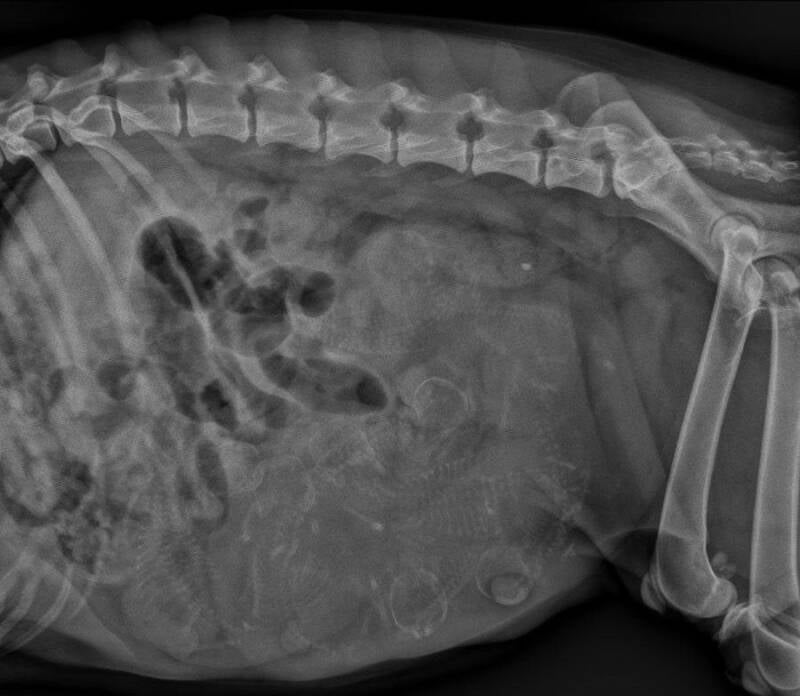

2 april zijn we weer bij de dierenarts geweest om een rontgen foto te maken.

Zodat we een beetje een idee hebben hoeveel pups we kunnen verwachten.

We hebben er 8 geteld. Beetje druk in de buik van Jiulia.

Het blijft spannend.........